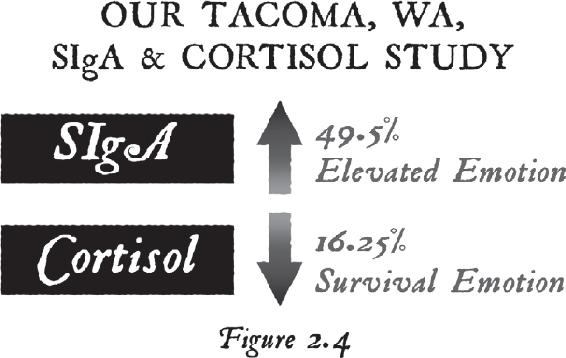

In fact, in the last four years my team of researchers, my staff, and I have gone through extensive strides to scientifically measure, record, and analyze these transformations in people’s biology to prove to the world that common people can do the uncommon. This book is about more than just healing, although it includes stories of people who have made significant changes in their health and have actually reversed diseases—along with the tools you need to do the same. These accomplishments are becoming quite common in our community of students. The material you are about to read lives outside of convention and is not usually seen or understood by most of the world. The content of this book is based on an evolution of teachings and practices that have culminated in our students’ ability to delve deeper into the more mystical of these. And of course, I am hoping it will bridge the world of science with the world of mysticism.

In the past, I hesitated to talk about this realm of reality because I feared it might divide an audience based on their own personal beliefs. However, I have wanted to write this book for a long time now. Over the years, I have had profoundly rich mystical experiences that have changed me forever. Those inner events have influenced who I am today. I want to introduce you to that world of dimension and show you some of the measurements we took and the studies we did in our advanced workshops around the world. I started collecting data on our students in these workshops because we witnessed significant changes in their health, and I knew they were changing their biology during the meditations—in real time.

We have also recorded amazing changes in heart rate variability (HRV). That’s when we know a student is opening their heart and maintaining elevated emotions like gratitude, inspiration, joy, kindness, appreciation, and compassion, which cause the heart to beat in a coherent fashion—that is, with rhythm, order, and balance. We know that it takes a clear intention (a coherent brain) and an elevated emotion (a coherent heart) to begin to change a person’s biology from living in the past to living in the future. That combination of mind and body—of thoughts and feelings—also seems to influence matter. And that’s how you create reality.

We know it’s true because our studies show significant changes in our students’ gene expression, and they’ve then reported significant changes in their health. Once we can show someone measurable results proving they truly have altered neurotransmitters, hormones, genes, proteins, and enzymes through thought alone, they can better justify their efforts and prove to themselves that they really are transforming.